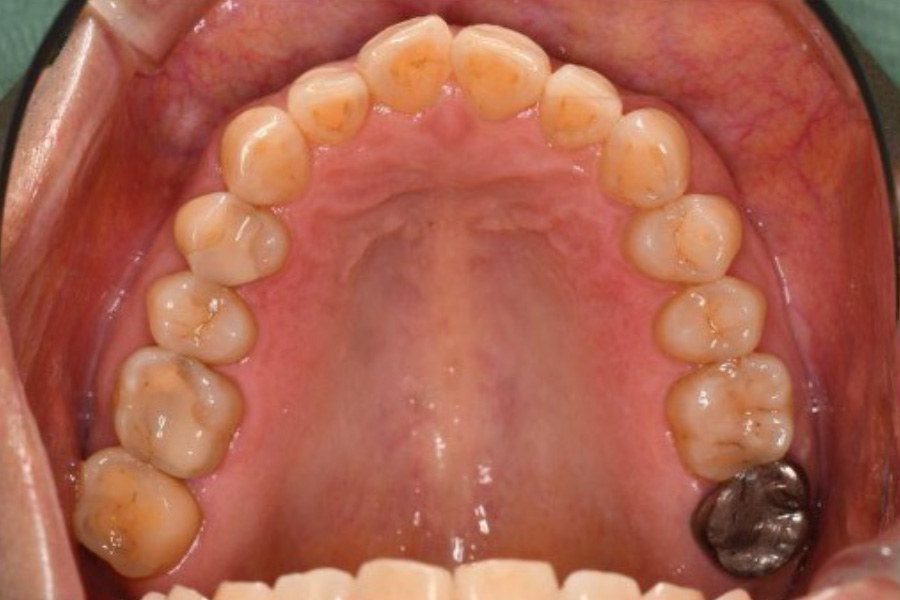

【口腔内写真】上顎咬合面

(上あごの噛み合わせ)の全景

上あごにおいても、歯を支える骨の幅が異常に大きく発達(骨隆起)しています。これは想定を超えた破壊的な荷重(オーバーロード)から歯を守ろうと、身体が必死に地盤を補強した痕跡です。

右上奥歯(6・7番)は、エナメル質が激しくすり減り、内部の象牙質が広範囲に露出しています。歯と歯の継ぎ目には荷重による「ヒビ(クラック)」が入り、そこから細菌の二次侵入を許しています。このまま放置すれば、いずれ歯が真っ二つに割れてしまう寸前の状態でした。

左上奥歯も同様に、重機で削り取ったかのような激しいすり減りが認められます。金属の被せ物には、繰り返された噛み合わせ調整の跡が深く刻まれており、いかに特定の部位に凄まじい力が集中していたかを物語っています。

お口全体の各所に見られる「ヒビに伴う虫歯」は、単なる磨き残しではなく、過度な力による構造破壊が引き金となって細菌の侵入を招いたものであり、根本的な「力のコントロール」が不可欠であることを示しています。